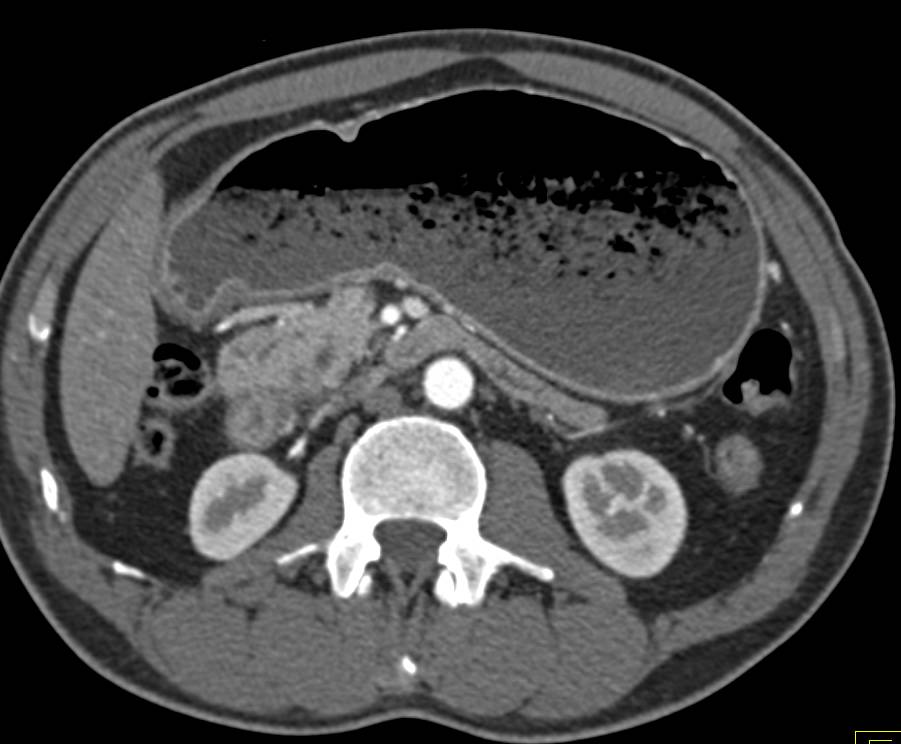

Carcinomatosis as well as Paracardiac Nodes